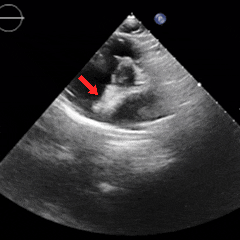

术后1周复查心脏彩超提示可降解封堵器形态位置良好,无残余分流,周围其他结构无异常。

术后1月随访

术后1月随访,患者自述症状较前明显减轻,复查心脏彩超提示可降解封堵器形态位置良好,无残余分流,周围其他结构无异常。